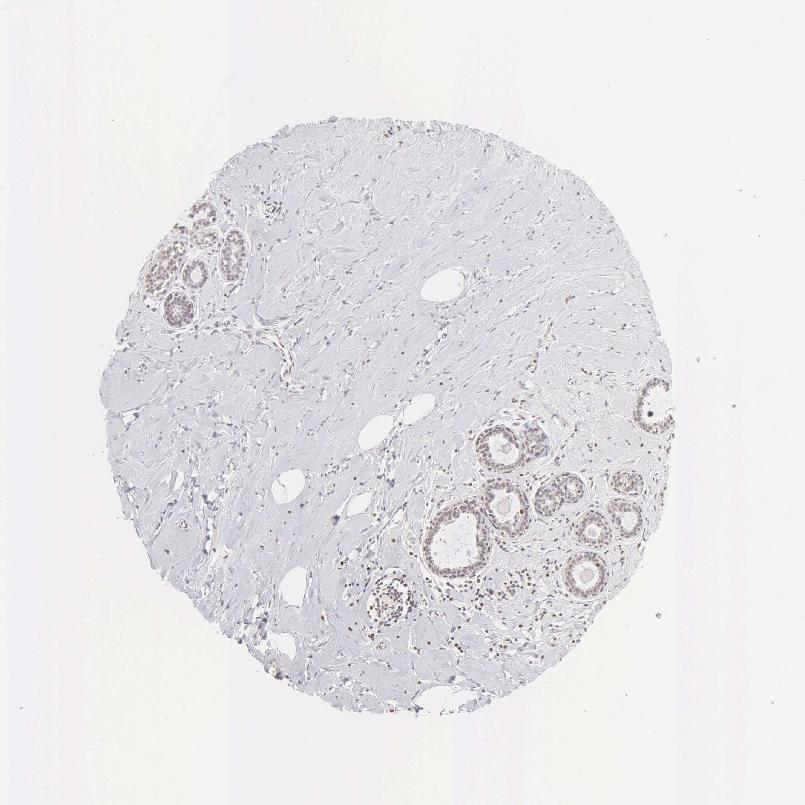

BREAST - Antibody stainingi

Antibody staining in the annotated cell types in the current human tissue is reported as not detected, low, medium, or high, based on conventional immunohistochemistry profiling in selected tissues. This score is based on the combination of the staining intensity and fraction of stained cells.

Each image is clickable and will lead to virtual microscopy that enables deeper exploration of all samples and also displays staining intensity scores, fraction scores and subcellular localization as well as patient and tissue information for each sample.

Antibody HPA000451Antibody HPA001164Antibody CAB000058Antibody CAB068198Antibody CAB080228

Adipocytes Not detectedNot detectedNot detectedNot detectedNot detected

Glandular cells LowHighMediumNot detectedMedium

Myoepithelial cells Not detectedNot detectedNot detectedNot detectedNot detected